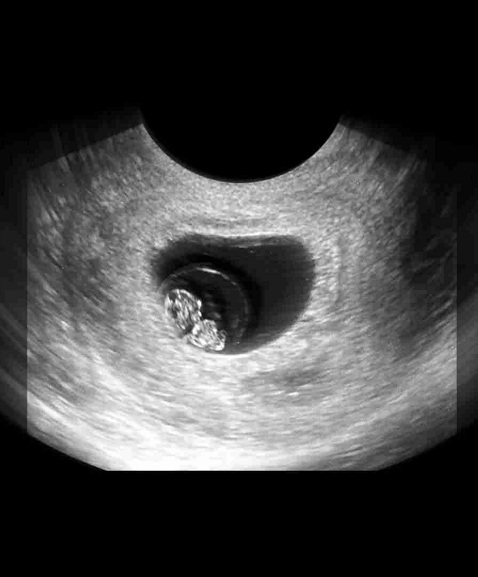

B超图

其次则是超音波检查,区分子宫内妊娠、葡萄胎、子宫外孕等状况,以及是否并发子宫或卵巢肿瘤,若能清楚看到胎心搏动,通常表示尚无大碍。